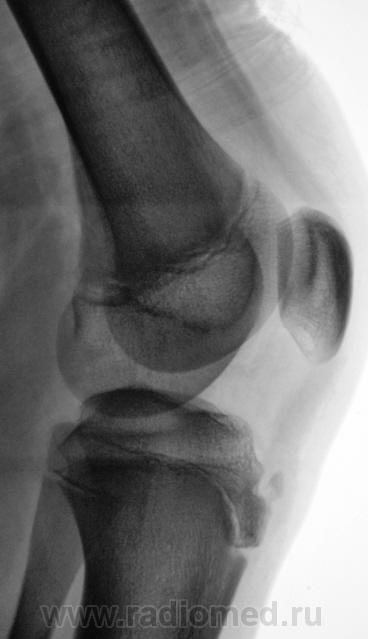

Пациент направлен на рентгенографию коленного сустава с диагнозом - Болезнь Осгут - Шлаттера.

фрагментация бугристости Б\Б кости

Болезнь Осгут - Шлаттера, как-то не вдохновляет. Более склонен к консоидирующемуся отрывному перелому бугристости б/берцовой кости.

Более склонен к варианту окостенения, хотя травматический генез, как и асептический некроз (абсолютно согласен с Максималистом - при наличии клиники и анамнеза) с повестки дня окончательно, до выяснения оных, не снимаются.

Уважаемые коллеги! На мой взгляд, выявленное на рентгенограмме, образование костной плотности, с четкими, ровными контурами, однородное по своей структуре отношения с бугристости большеберцовой кости не имеет. Хотелось бы знать возраст пациента, его анамнез (спорт, травмы области коленного сустава). Больше похоже на обызвествления собственной связки надколенника. Дополнил бы УЗИ коленного сустава.

16 лет "учтенному лицу", ранее жалоб не было, рядом "мама", которой доктора посоветовали..., вот и вся история...